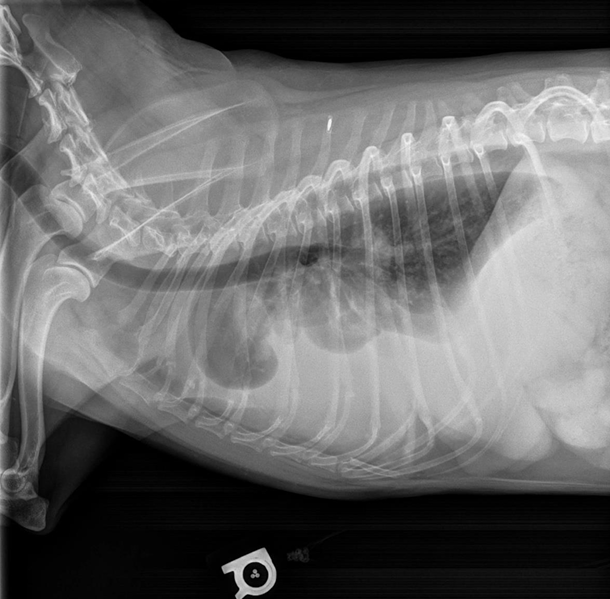

Diagnosis

- Radiographs : 최대 흡기, 최대 호기 둘 다 촬영 !!

- 최대 흡기 시 extrathoracic trachea의 lumen size

- 최대 호기 시 intrathoracic trachea의 lumen size

- 식도가 기관을 누르거나, 식도가 겹쳐 가려질 수 있으니 판독 시 주의.

- Fluoroscopic evaluation : 움직이는 영상으로 관찰 가능.